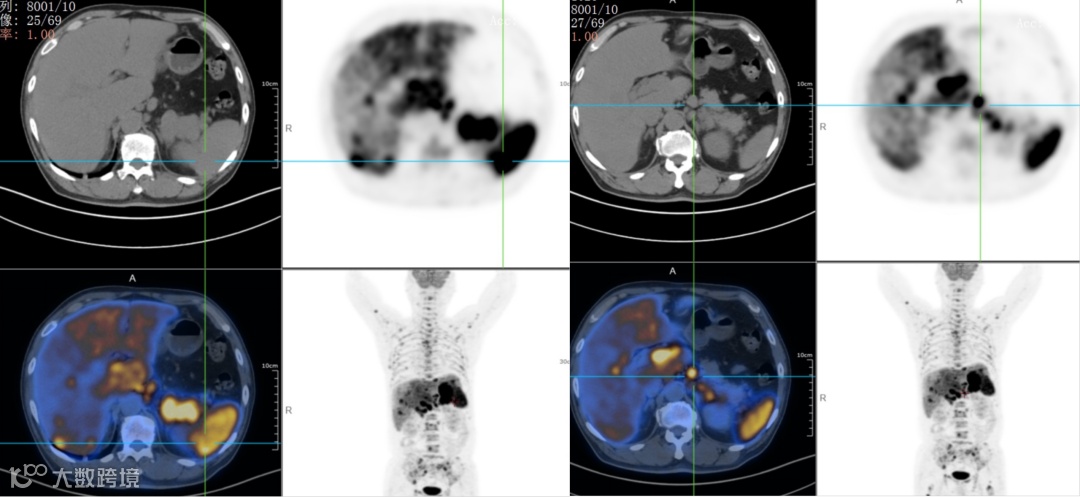

双侧内乳区、膈上、右侧膈肌脚区、肝门区、肝胃间隙、脾门区、腹膜后多发淋巴结,肝脾肿大,代谢增高;脊柱多个椎体及部分附件、双侧肱骨、双侧肩胛骨、双侧锁骨、双侧多根肋骨、胸骨、骨盆诸组成骨、双侧股骨上段多发代谢异常增高灶。